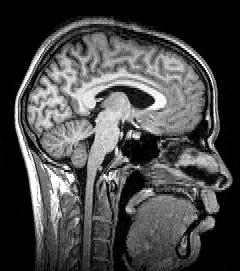

Para-sagittal MRI of the head in a patient with benign familial macrocephaly.